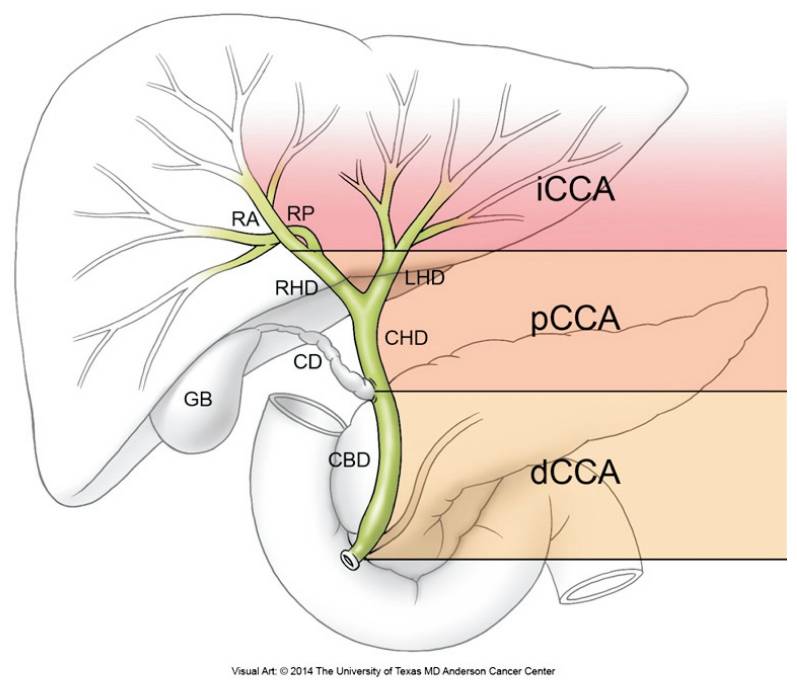

COLANGIOCARCINOMA

O colangiocarcinoma é o câncer derivado das células biliares, tanto no interior quanto no exterior do fígado (vesícula e ductos biliares), sendo o segundo câncer primário mais comum do fígado. Surge principalmente em homens (3 homens para cada mulher), geralmente entre os 70 e 80 anos com uma incidência dessa doença é de 2 a 2,8 casos a cada 100.000 pessoas.

Na maioria das vezes o colangiocarcinoma é esporádico, ou seja, sem uma causa clara. As pessoas de maior risco são aquelas portadoras de parasitas das vias biliares (raros no Brasil), colangite esclerosante primária (outra doença que pode levar à cirrose), colite ulcerativa (doença que leva a diarreia crônica, com episódios de sangramento, em adultos jovens), cálculos biliares, doença de Caroli e cistos de colédoco (tipos I e IV).

Esse tipo de câncer cresce silenciosamente nos canais biliares até que estes sejam obstruídos, levando aos sintomas de icterícia, fezes claras e urina escura, além de perda do apetite e emagrecimento. Ocasionalmente, pode ser descoberto em exames de rotina ou durante o acompanhamento de pacientes com colangite esclerosante primária.

O diagnóstico geralmente é realizado por exames de imagem, sendo a ressonância nuclear magnética o exame de escolha, particularmente a colangiorressonância (RNM realizada com foco no estudo das vias biliares). A colangiopancreatografia retrógrada endoscópica (CPRE) pode ser realizada quando for necessário colher material para biópsias ou para a colocação de próteses para desobstruir e manter as vias biliares abertas.

Atualmente, o único grupo de pacientes com indicação de exame radiológico (não invasivo) de rastreamento do colangiocarcinoma é o de portadores de colangite esclerosante primária, pois esses tem um risco de 20% de desenvolver esse tipo de câncer ao longo da vida. Não está bem claro qual o melhor método de rastreamento, mas a recomendação atual da sociedade européia (EASL) é de ressonância com colangiorressonância anualmente. Se o paciente está em fase de cirrose, o rastreamento é o mesmo que para o hepatocarcinoma, com ultrassom semestral.

Infelizmente, o diagnóstico ainda é feito tardiamente, já que a maioria dos pacientes não têm fatores de risco claros e os sintomas surgem com a doença mais avançada. O tratamento ideal é a cirurgia, mas ela só é realizável em menos de um terço dos pacientes. É uma cirurgia grande, de risco, mas com possibilidade de cura quando possível, especialmente quando associada a quimio ou radioterapia. Quando não é possível, medidas paliativas como as descritas para o hepatocarcinoma podem ser empregadas. O transplante hepático só é realizado em casos muito selecionados pelo alto risco de recidiva após o transplante.